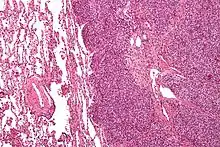

| Micrograph of metastatic Ewing sarcoma (right of image) in normal lung (left of image). PAS stain. | |

Ewing sarcoma is a small-blue-round-cell tumor that typically has a clear cytoplasm on H&E staining, due to glycogen. The presence of the glycogen can be demonstrated with positive PAS staining and negative PAS diastase staining. The characteristic immunostain is CD99, which diffusely marks the cell membrane. However, as CD99 is not specific for Ewing sarcoma, several auxiliary immunohistochemical markers can be employed to support the histological diagnosis.[23] Morphologic and immunohistochemical findings are corroborated with an associated chromosomal translocation, of which several occur. The most common translocation, present in about 90% of Ewing sarcoma cases, is t(11;22)(q24;q12),[24][25] which generates an aberrant transcription factor through fusion of the EWSR1 gene with the FLI1 gene.[26]